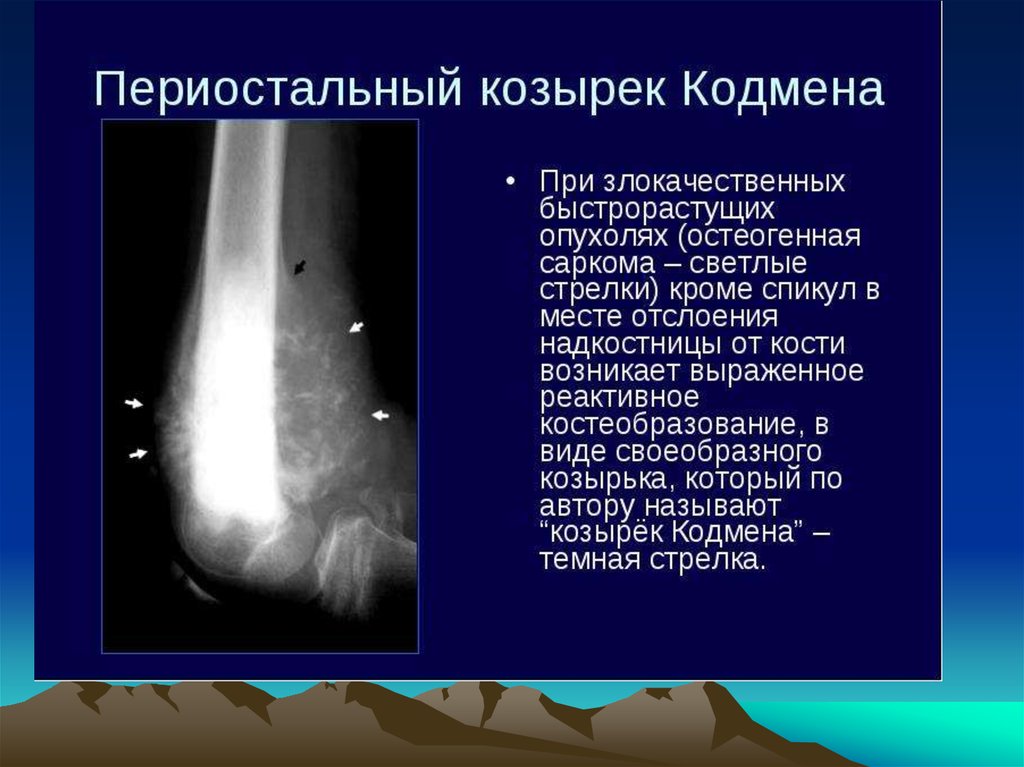

Рентгенологическая картина остеогенной саркомы кости - 98 фото